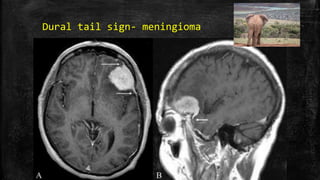

Dural tail sign- meningioma

• #71 Dural tail sign. Axial (A) and sagittal (B) contrast-enhanced MRI images of the brain show an avidly enhancing lesion in the left frontal region. The lesion is dural based and there is thickening and enhancement of the dura, which tapers away from the mass (arrows). This thickening and enhancement of the dura adjacent to the mass is the ‘dural tail sign’ that is seen in meningiomas